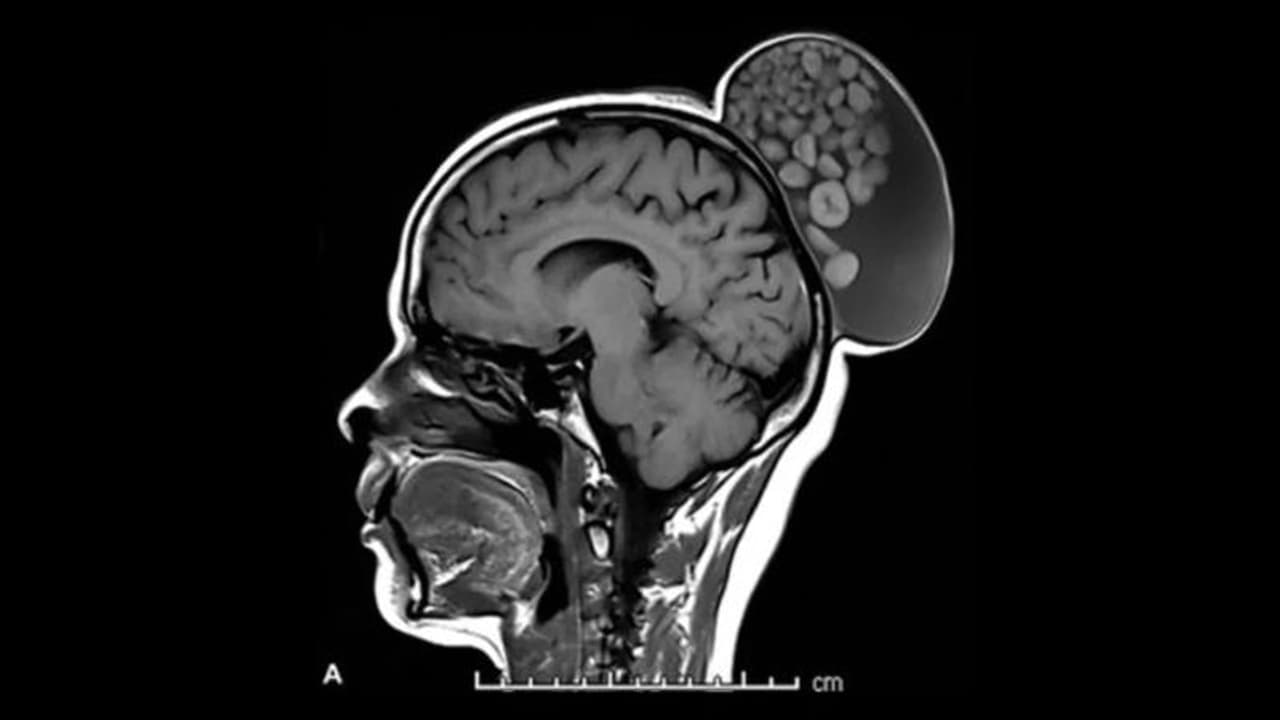

எம்ஆர்ஐ ஸ்கேன் செய்ததில், அவளது தலையின் பின்பகுதியில் ஒரு சதைப்பற்றுள்ள வளர்ச்சி இருப்பது தெரியவந்தது. வளர்ச்சியை அகற்ற அறுவை சிகிச்சையின் போது, திரவம், முடி, கொழுப்பு மூலக்கூறுகள் மற்றும் கெட்டியான வெளிப்புற விளிம்புகள் கொண்ட கெரட்டின் பந்துகள் ஆகியவற்றால் நிரப்பப்பட்டிருப்பதை மருத்துவர்கள் கண்டறிந்தனர்.

கெரட்டின் என்பது ஒரு புரதமாகும். இது முடி, நகங்கள் மற்றும் தோலின் வெளிப்புற அடுக்குக்கு அடிப்படையாக அமைகிறது. வளர்ச்சியில் காணப்படும் வெகுஜனங்கள் டெர்மாய்டு நீர்க்கட்டிகள் என்று அழைக்கப்படுகின்றன. அவை கரு உயிரணுக்களிலிருந்து உருவாகின்றன. முடி, பற்கள் அல்லது நரம்புகளைக் கொண்டிருக்கலாம். அவை பெரும்பாலும் தலை மற்றும் கழுத்து பகுதியில் தோன்றும் போது, அவை கருப்பைகள் அல்லது உடலின் பிற பகுதிகளிலும் இருக்கலாம்.